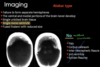

AQUEDUCTAL STENOSIS:

-congenital causes?

congenital causes:

aqueductal webs or diaphragms / gliosis